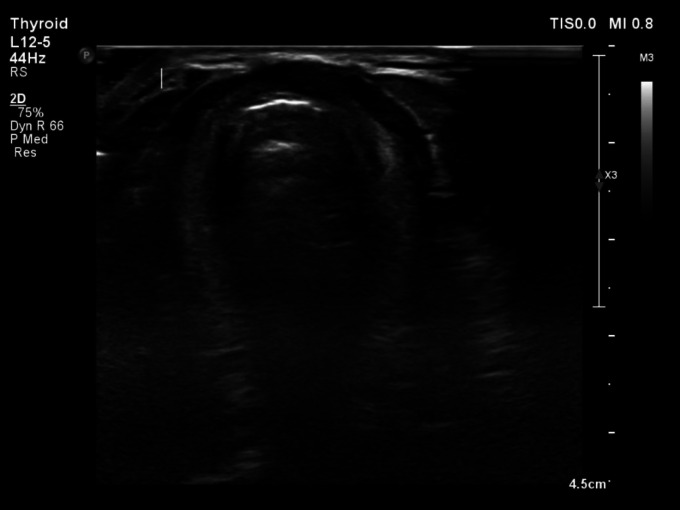

Ectopic thyroid tissue is a rare congenital anomaly, with the presence of three simultaneous ectopic foci being exceedingly rare. We describe a case of a totally asymptomatic 26-year-old male discovered to have triple ectopic thyroid following incidental elevated thyroid-stimulating hormone (TSH) levels. Subsequent ultrasonography of the neck showed an absent thyroid gland in its conventional location. A Technetium-99m pertechnetate (Tc-99m) thyroid scan showed three distinct foci of radiotracer uptake in the upper cervical, lingual, and sublingual regions, corresponding to triple ectopic thyroid. An extensive review of the literature was conducted to provide a broader understanding and deeper insights into this uncommon condition. This case underscores the pivotal role of Technetium-99m thyroid scanning in diagnosing triple ectopic thyroid, particularly in instances where the orthotopic thyroid gland is absent. A comprehensive understanding of this rare entity is indispensable for radiologists and clinicians, enabling accurate diagnosis and informed decision-making regarding the appropriate therapeutic strategies.